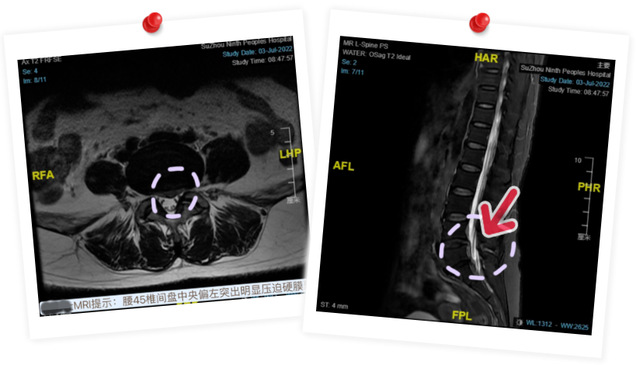

患者沈女士在入院2天前突发会阴部麻木及双下肢麻木无力,当时未予重视,直至小便不能自解,腹部膨隆才来院就诊。经入院进一步检查,被诊断为“马尾综合征”。

一旦马尾神经受损,患者受伤平面以下可表现出弛缓性瘫痪、感觉和运动障碍,包括约肌功能丧失、腱反射消失,也就是我们通常所见到的下肢及会阴部周围麻木疼痛、大小便失禁、软瘫等症状。“马尾综合征”一直是临床疑难课题,越早手术解除神经受压,神经功能恢复的希望就越大。

骨科主任言湛军介绍,“马尾综合征”是腰椎间盘突出、腰椎管狭窄、腰椎外伤或肿瘤等原因引起的一种临床表现,往往提示神经功能严重受损,耽误越久,神经功能恢复状况越严峻。因此,出现“马尾综合征”必须在确保患者生命安全的前提下尽早进行手术。